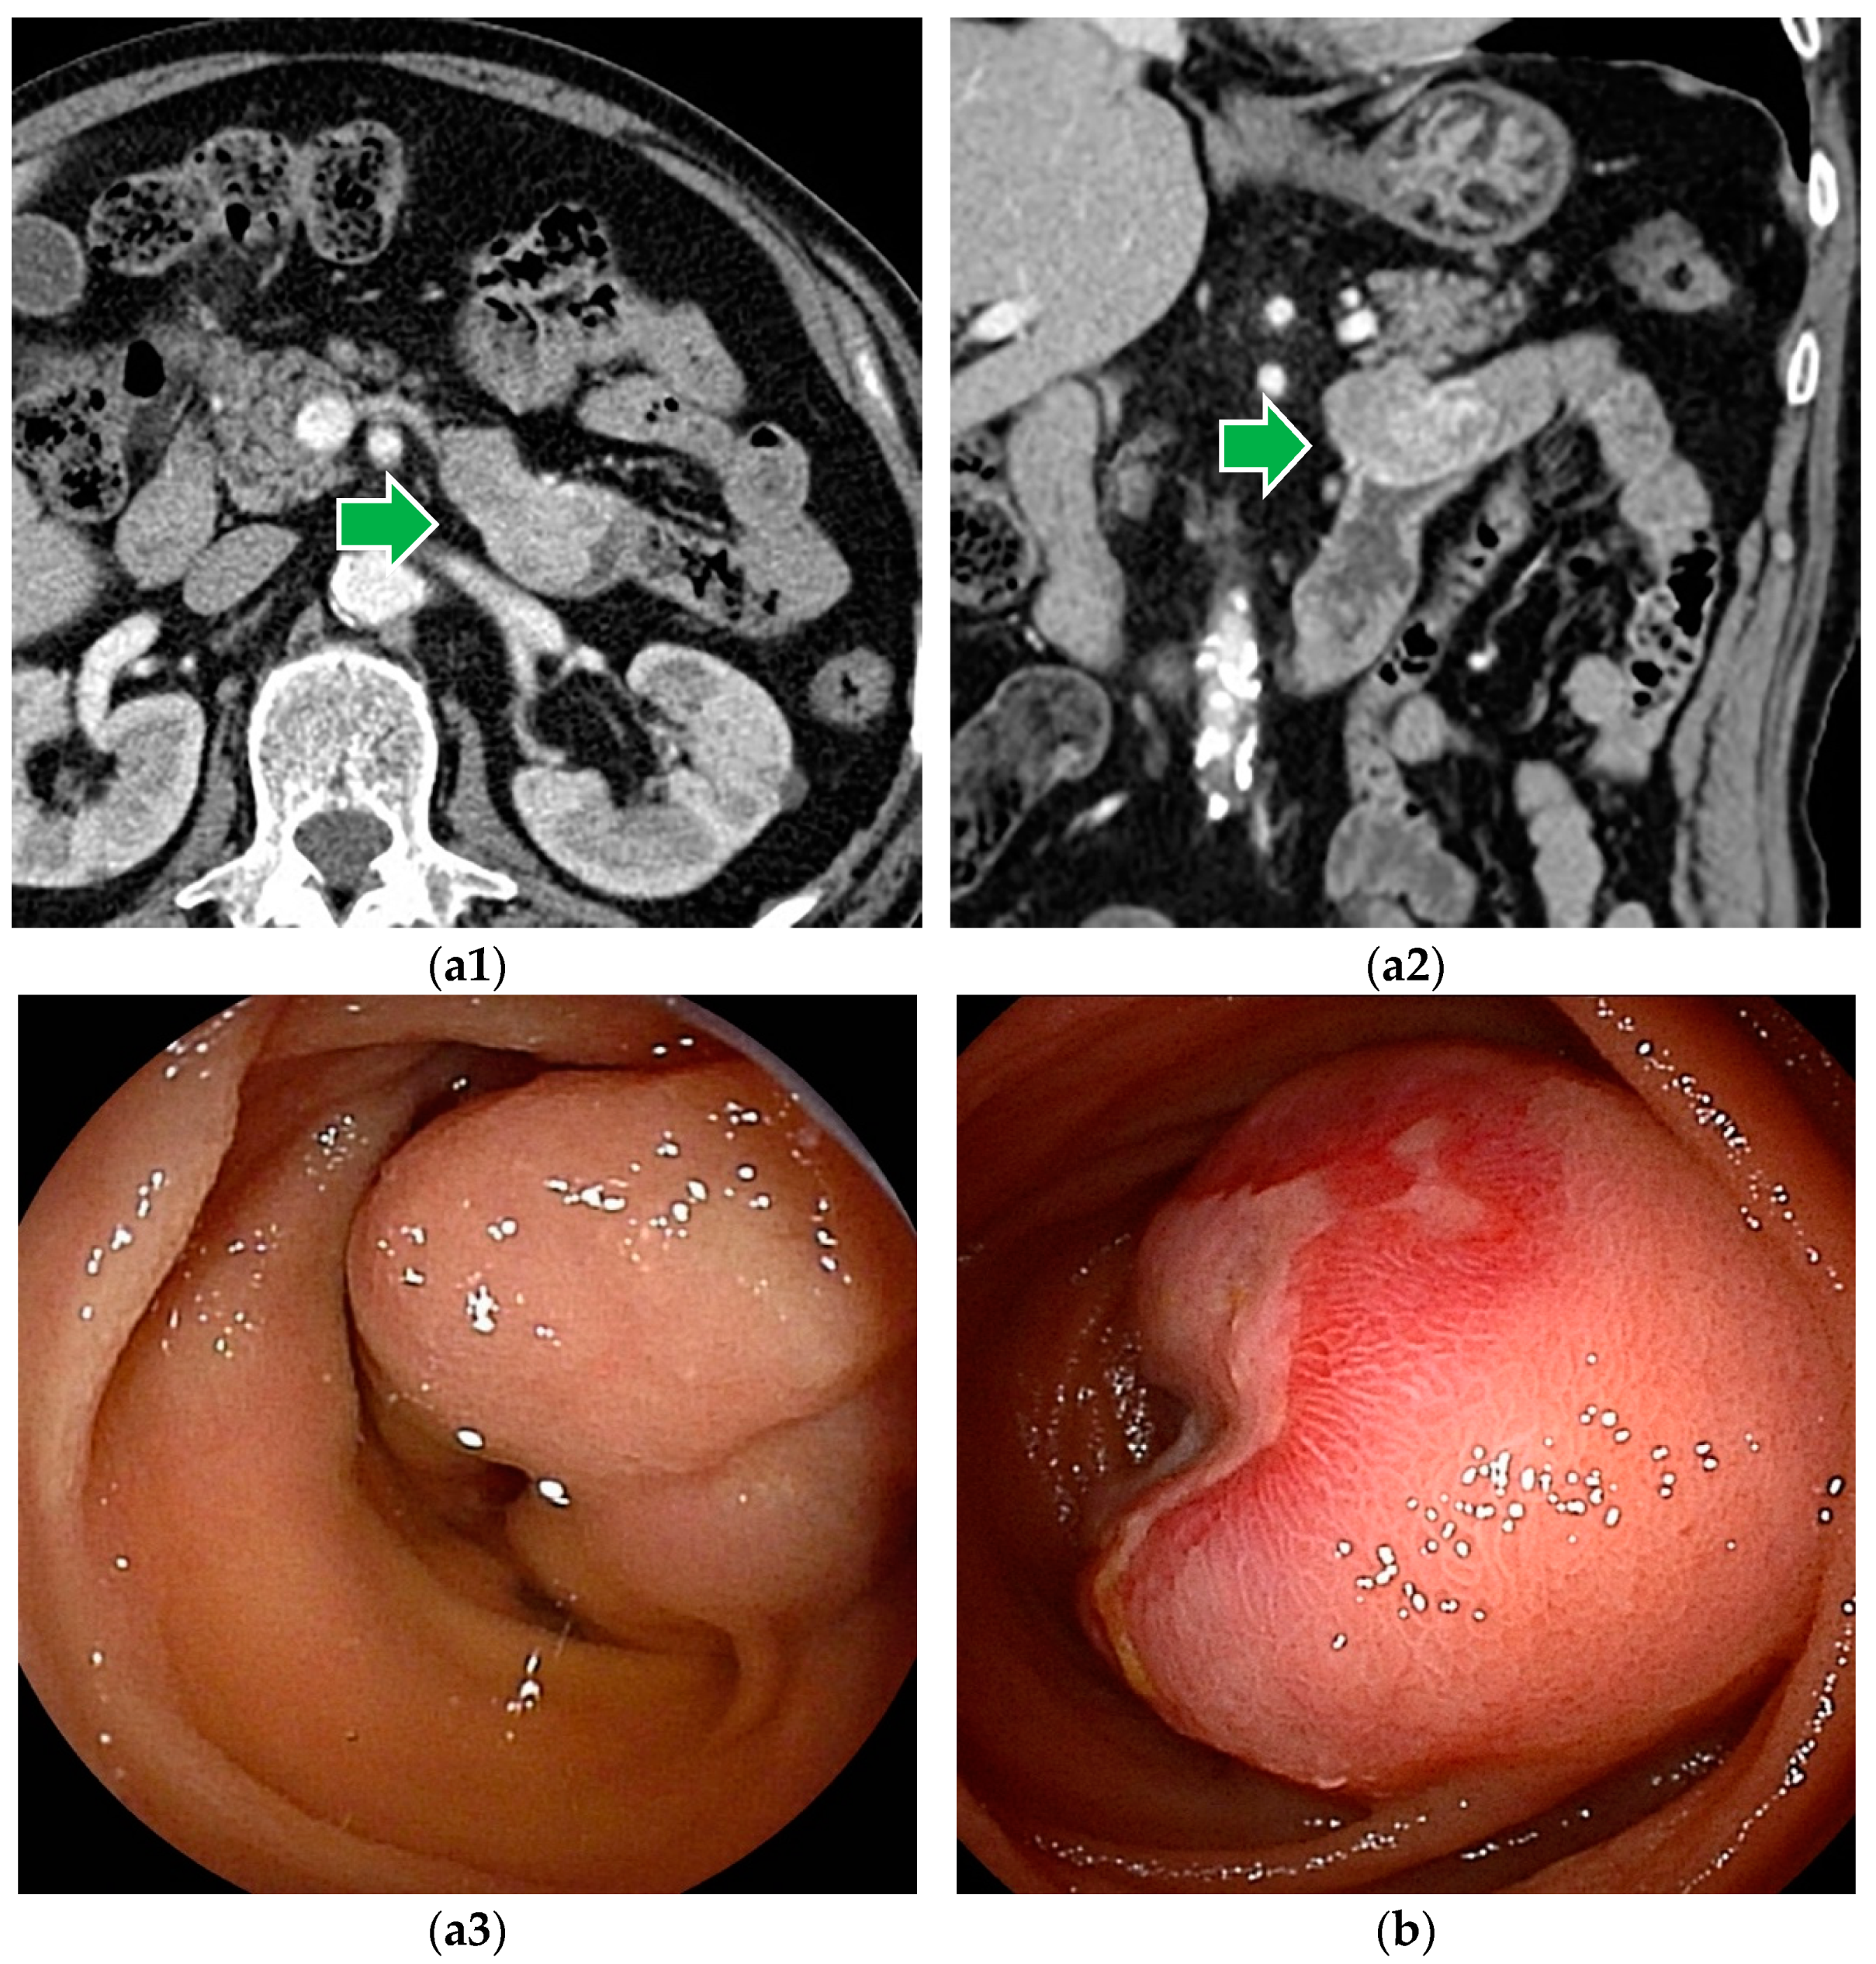

Figure 2.

Gastrointestinal stromal tumor (GIST): (a1–a3) Contrast-enhanced CT revealed a well-enhanced lesion. DBE showed a submucosal tumor covered by normal mucosa. (b) In patients with bleeding symptoms, erosions, ulcers, or dilated blood vessels are seen on the surface.

Although GIST with intraluminal and mixed patterns can be detected by BAE (Figure 2), GIST with extraluminal patterns is hardly detected by endoscopy, except for abnormal vessels and unnatural traction findings due to lesions.